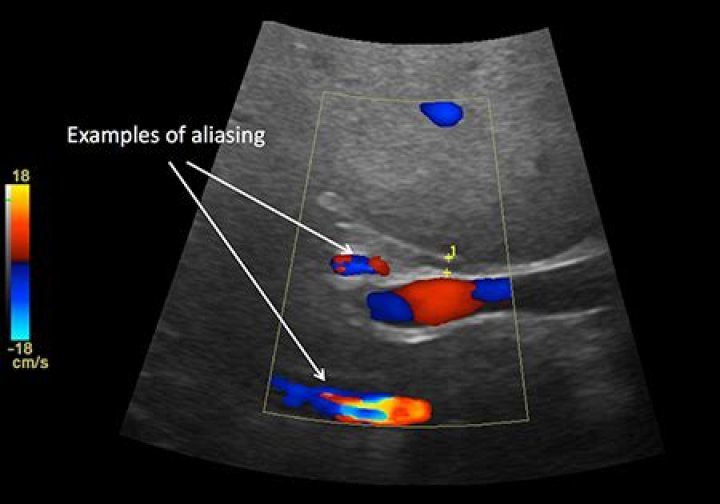

Aliasing phenomenon is a concept that causes a lot of uncertainty for many of us. … We see examples of aliasing in both colour and spectral Doppler, where the velocity exceeds the Nyquist Limit and the image displayed would suggest flow is heading in the opposite direction.

Aliasing. Aliasing arises when the Doppler shift of the moving blood is higher than half of the PRF (Nyquist limit). Aliased signals are displayed with the wrong direction (red instead of blue and vice versa) and velocity (the hue of the colour) (Fig.